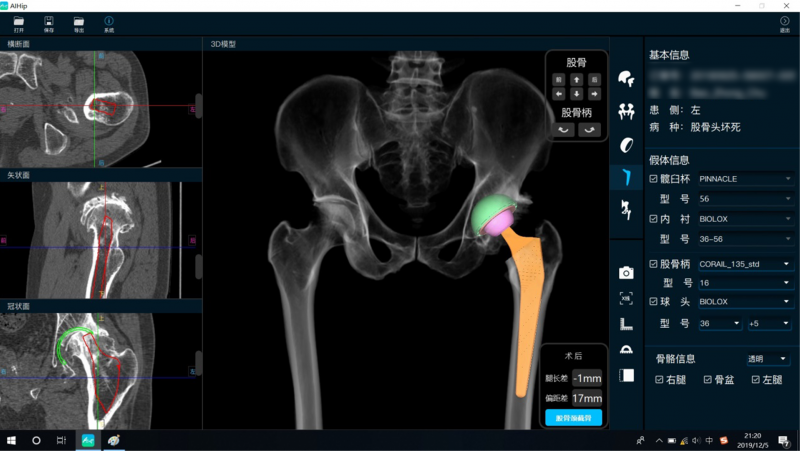

为此,骨关节科借助“AI HIP-全髋关节人工智能辅助诊疗系统”,让人工智能技术收集患者横断面的髋关节CT影像,重建出三维立体影像,并对股骨偏心距与双侧腿长差进行智能测量与评估,计算出腿长差为12mm,左侧(患侧)股骨偏心距较左侧缩减了24mm。同时,系统将臼杯计划的大小、安放的最佳位置以及安放之后臼杯的深度、高度、前后髋臼壁对臼杯的夹持情况等直观地展现出来,并把规划好的模拟X线影像提供给手术医生。

“AI HIP-全髋关节人工智能辅助诊疗系统”可以很好地帮助医生完成关节置换手术的术前规划、假体选择等工作